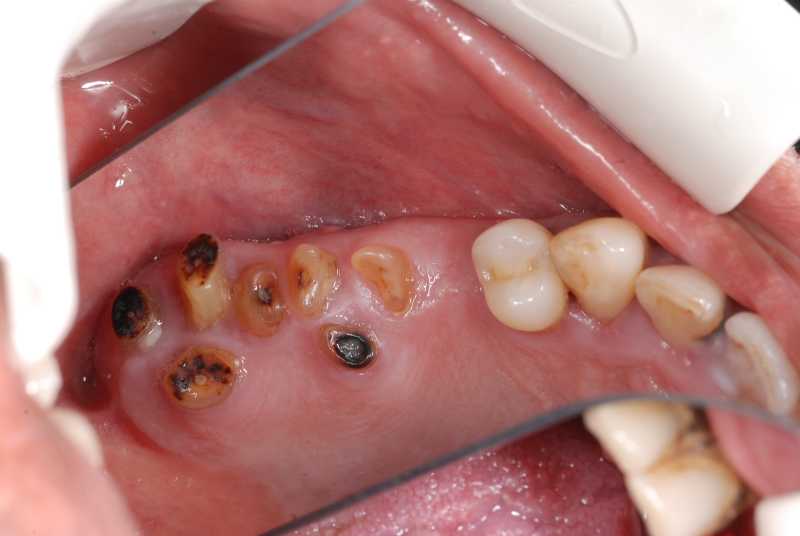

Inicio Especialidades Cirurgia